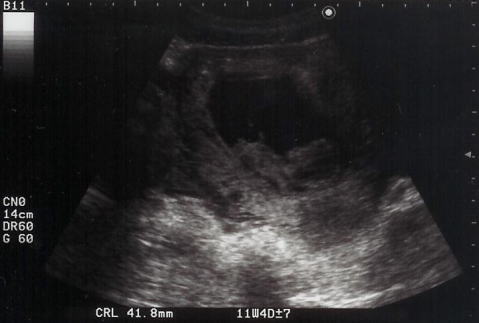

2004年10月1日(金)

11週4日

暗くて見えにくいけど、大きな頭と手が見えます。ママやパパと同じ形になりました。

ママは初期検査でした。そして、初めてshigeruの心音を聞かせてもらいました。ものすごいスピードでしたが、お腹にいる赤ちゃんはみんな大人の倍のスピードで動いているそうです。もう出血もありません。つわりがもう少しで終わることを期待しているママでした。

写真中央で2頭身shigeruが仰向けになっている